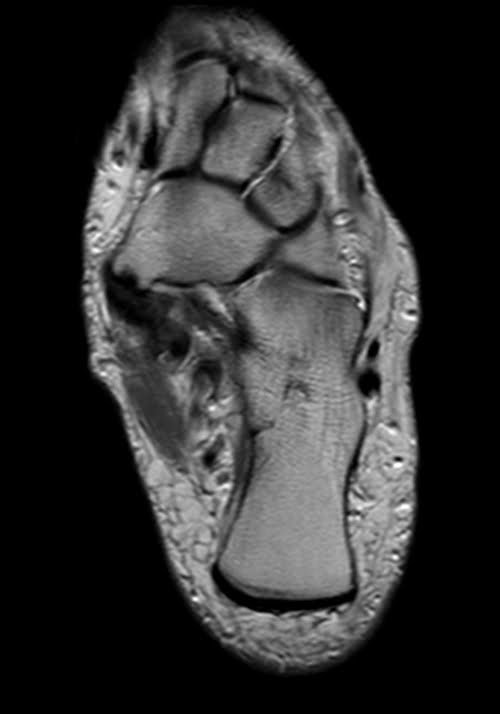

MRI ANKLE AXIAL PD IMAGE 1 - MRI